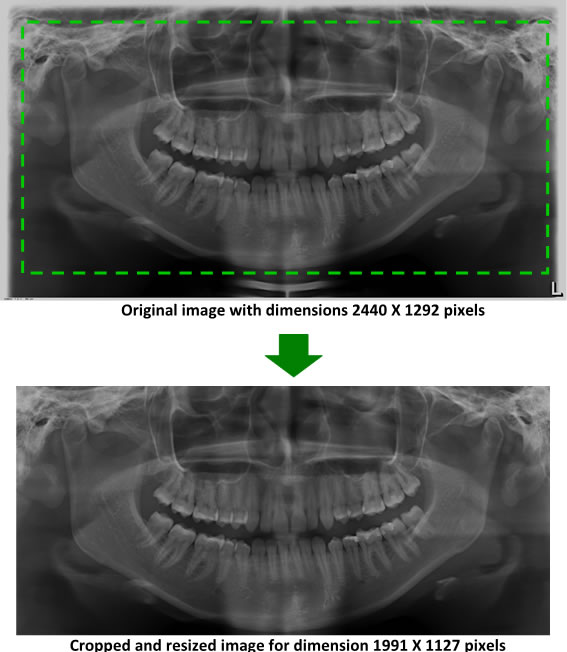

To thoroughly benchmark the methods studied here, the 1,500 images were distributed among 10 categories. The images were named, using whole numbers, in sequential order by category, aiming at not identifying the patients in the study. The process of categorizing the images was performed manually, selecting images individually, counting tooth by tooth, as well as verifying structural characteristics of the teeth. The images were classified according to the variety of structural characteristics of the teeth (see Table 5). Finally, the images were cut out to disregard non-relevant information (white border around the images and part of the spine) generated by the orthopantomograph device. After the clipping process, there was a change in the size of the images to 1991 1127 pixels, but without affecting the objects of interest (teeth), as shown in Figure 2. The cropped images were saved on the new dimension to be used in the following stages, which will be presented in the next sections. Figure 3 shows an X-ray image corresponding to each of the categories of our data set.